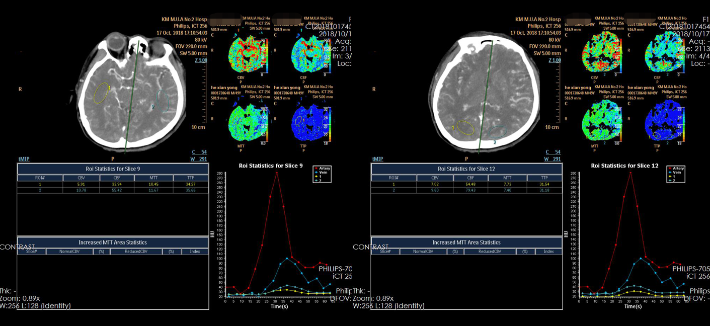

CTP

--CTP有低灌表现